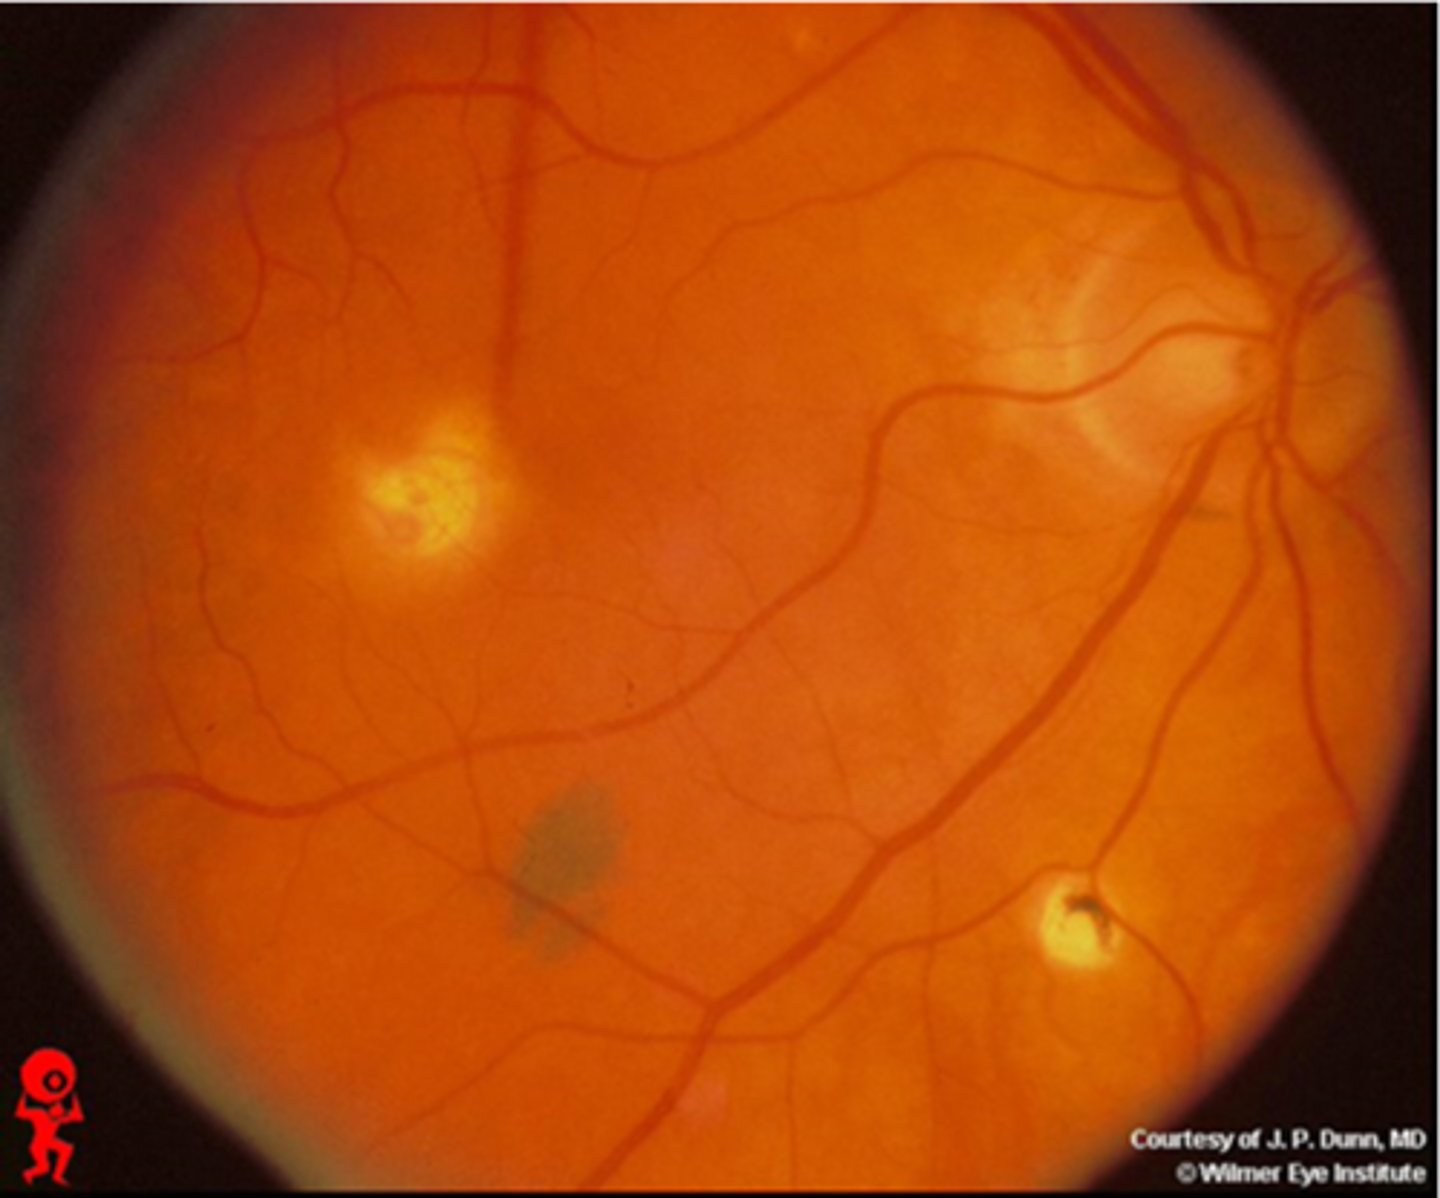

What findings of toxoplasmosis are seen here?

latent scars